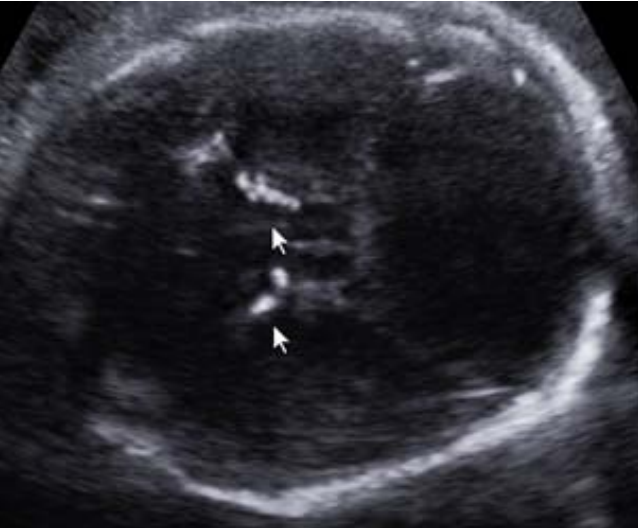

Paciente na 28ª semana, multípara, seis partos vaginais e sem pré-natal adequado vem à emergência obstétrica preocupada para mostrar uma ultrassonografia, a qual descreve uma circunferência cefálica abaixo de três desviospadrões para a idade gestacional e imagem abaixo:

Enunciado 3531304-1

Foi encaminhada para um serviço especializado, onde foi submetida à investigação diagnóstica. Na 39ª semana de gravidez, evoluiu com o parto vaginal. Ao nascimento, as alterações ultrassonográficas foram confirmadas, acrescidas de coriorretinite e atraso no desenvolvimento neurológio.

Baseado nesses sinais e sintomas, assinale a alternativa que sugere a principal hipótese etiológica fetal.